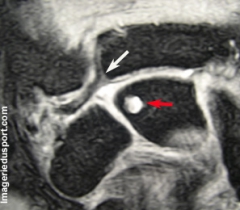

3/ chondromalacie le plus souvent focale au début, mais trés symptomatique

sclérose et remaniement kystique sous chondral, à un stade tardif

- prédomine au lunatum (excentrique sur le bord ulnaire)

- moins fréquent au niveau du triquetrum (bord radial) et encore plus rare au niveau de la tête de l'Ulna  (alors que dans le cadre du syndrome d'impingment ulnaire, les remaniements prédominent au niveau de l'extrémité distale de l'ulna)